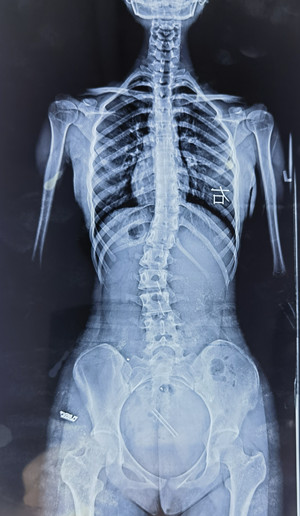

脊柱側(cè)彎的X線檢查

通過(guò)全脊柱正、側(cè)位X線檢查,能明確側(cè)彎的部位、角度、性質(zhì)、椎體旋轉(zhuǎn)程度等。要避免僅拍攝脊柱單部位X線片,因?yàn)槠潆y以充分顯示脊柱全貌,對(duì)診斷脊柱側(cè)彎來(lái)說(shuō)是局限的。

在X線檢查中,我們可以測(cè)定患者的cobb角,該角度測(cè)量是通過(guò)測(cè)量脊柱上下彎曲最頂端的兩個(gè)椎體上、下緣所成的角度,來(lái)確定側(cè)彎的嚴(yán)重程度。